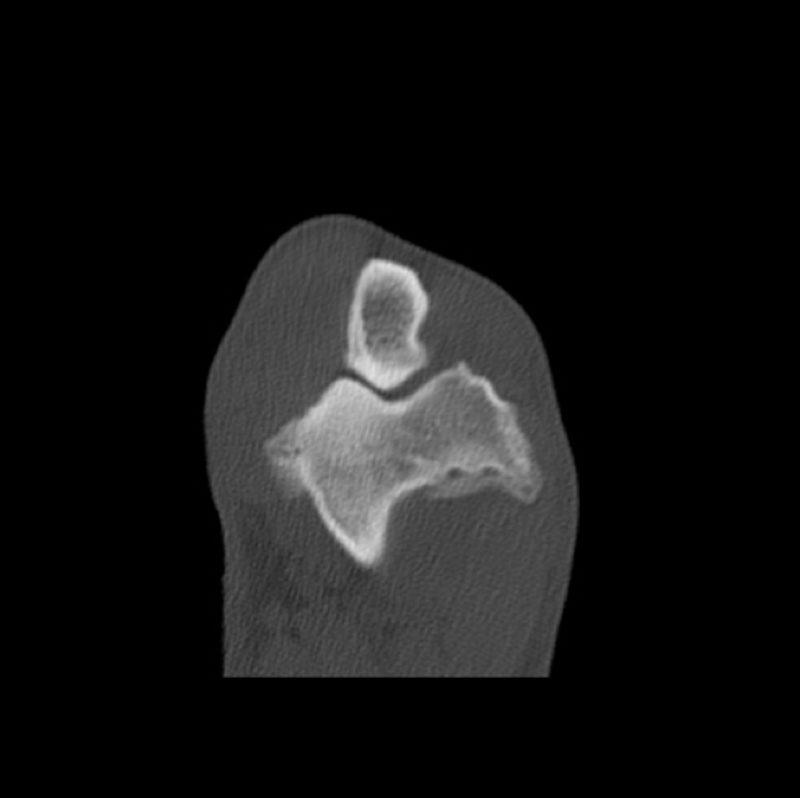

In den nächsten Tagen erhielt der Hund ein Schmerzmittel und Hyaluronsäure zum Knorpelaufbau und ging regelmäßig zur Physiotherapie. Aaron lief vier Wochen lahmfrei ohne Schmerzmittel. Danach ging er wieder zunehmend lahm. Er zeigte wieder deutliche Gelenkergüsse in beiden Ellenbögen. Es wurde eine Computertomographie-Untersuchung (CT) beider Ellenbögen durchgeführt. Im CT wurden mehrere osteophytäre Zubildungen (Arthrosen) am Gelenk diagnostiziert, welche infolge des permanenten Entzündungsreizes entstanden sind. Weitere knöcherne Veränderungen und eine erneute abgelöste Knorpelschuppe (OCD) konnte nicht gefunden werden.